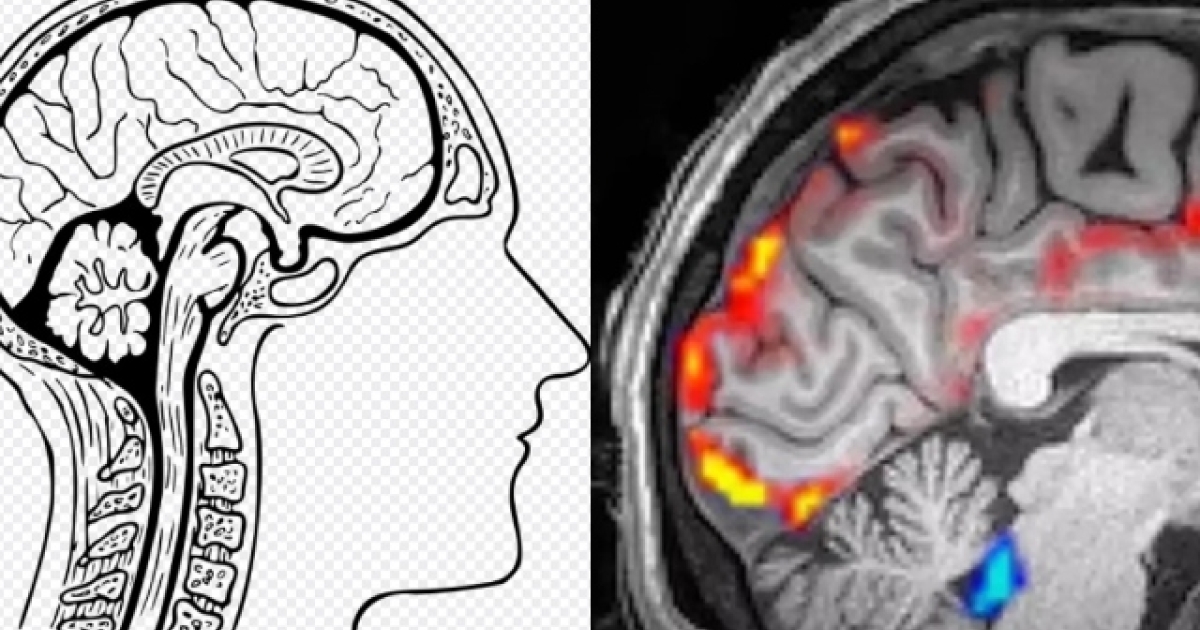

Η μελέτη εξηγεί: «Δεν είναι γνωστό αν αυτές οι δύο διαδικασίες σχετίζονται μεταξύ τους. Χρησιμοποιήσαμε επιταχυνόμενη νευροαπεικόνιση για να μετρήσουμε τη φυσιολογική και νευρωνική δυναμική στον ανθρώπινο εγκέφαλο».

Για τη μελέτη, 13 άτομα ηλικίας 23-33 ετών προσλήφθηκαν για να ξαπλώσουν μέσα σε ένα μηχάνημα μαγνητικής τομογραφίας και να κοιμηθούν.

Στη συνέχεια, το μηχάνημα μαγνητικής τομογραφίας κατέγραψε εικόνες από το ΕΝΥ του εγκεφάλου των συμμετεχόντων.

Και οι εικόνες αποκάλυψαν ότι ο εγκέφαλός σας είναι πολύ πιο ενεργός από ό,τι ίσως να φαντάζεστε όταν ακουμπάτε το κεφάλι σας στο μαξιλάρι.

Ουσιαστικά, όταν κοιμόμαστε ένα κύμα φρέσκου ΕΝΥ εισέρχεται στον εγκέφαλο και ξεπλένει τυχόν επιβλαβείς πρωτεΐνες (αυτές που μπορούν να αυξήσουν τον κίνδυνο της νόσου Αλτσχάιμερ). Αυτό το πλύσιμο συμβαίνει κάθε 20 δευτερόλεπτα. Το συγκεκριμένο μοτίβο χαρακτηρίστηκε ως «εντυπωσιακό» από τη νευροεπιστήμονα και μηχανικό του Πανεπιστημίου της Βοστώνης και συν-συγγραφέα της μελέτης Laura Lewis, η οποία έχοντας δει τα εντυπωσιακά αποτελέσματα της μελέτης τόνισε πόσο σημαντικός είναι ο ύπνος για τον καθαρισμό του εγκεφάλου.